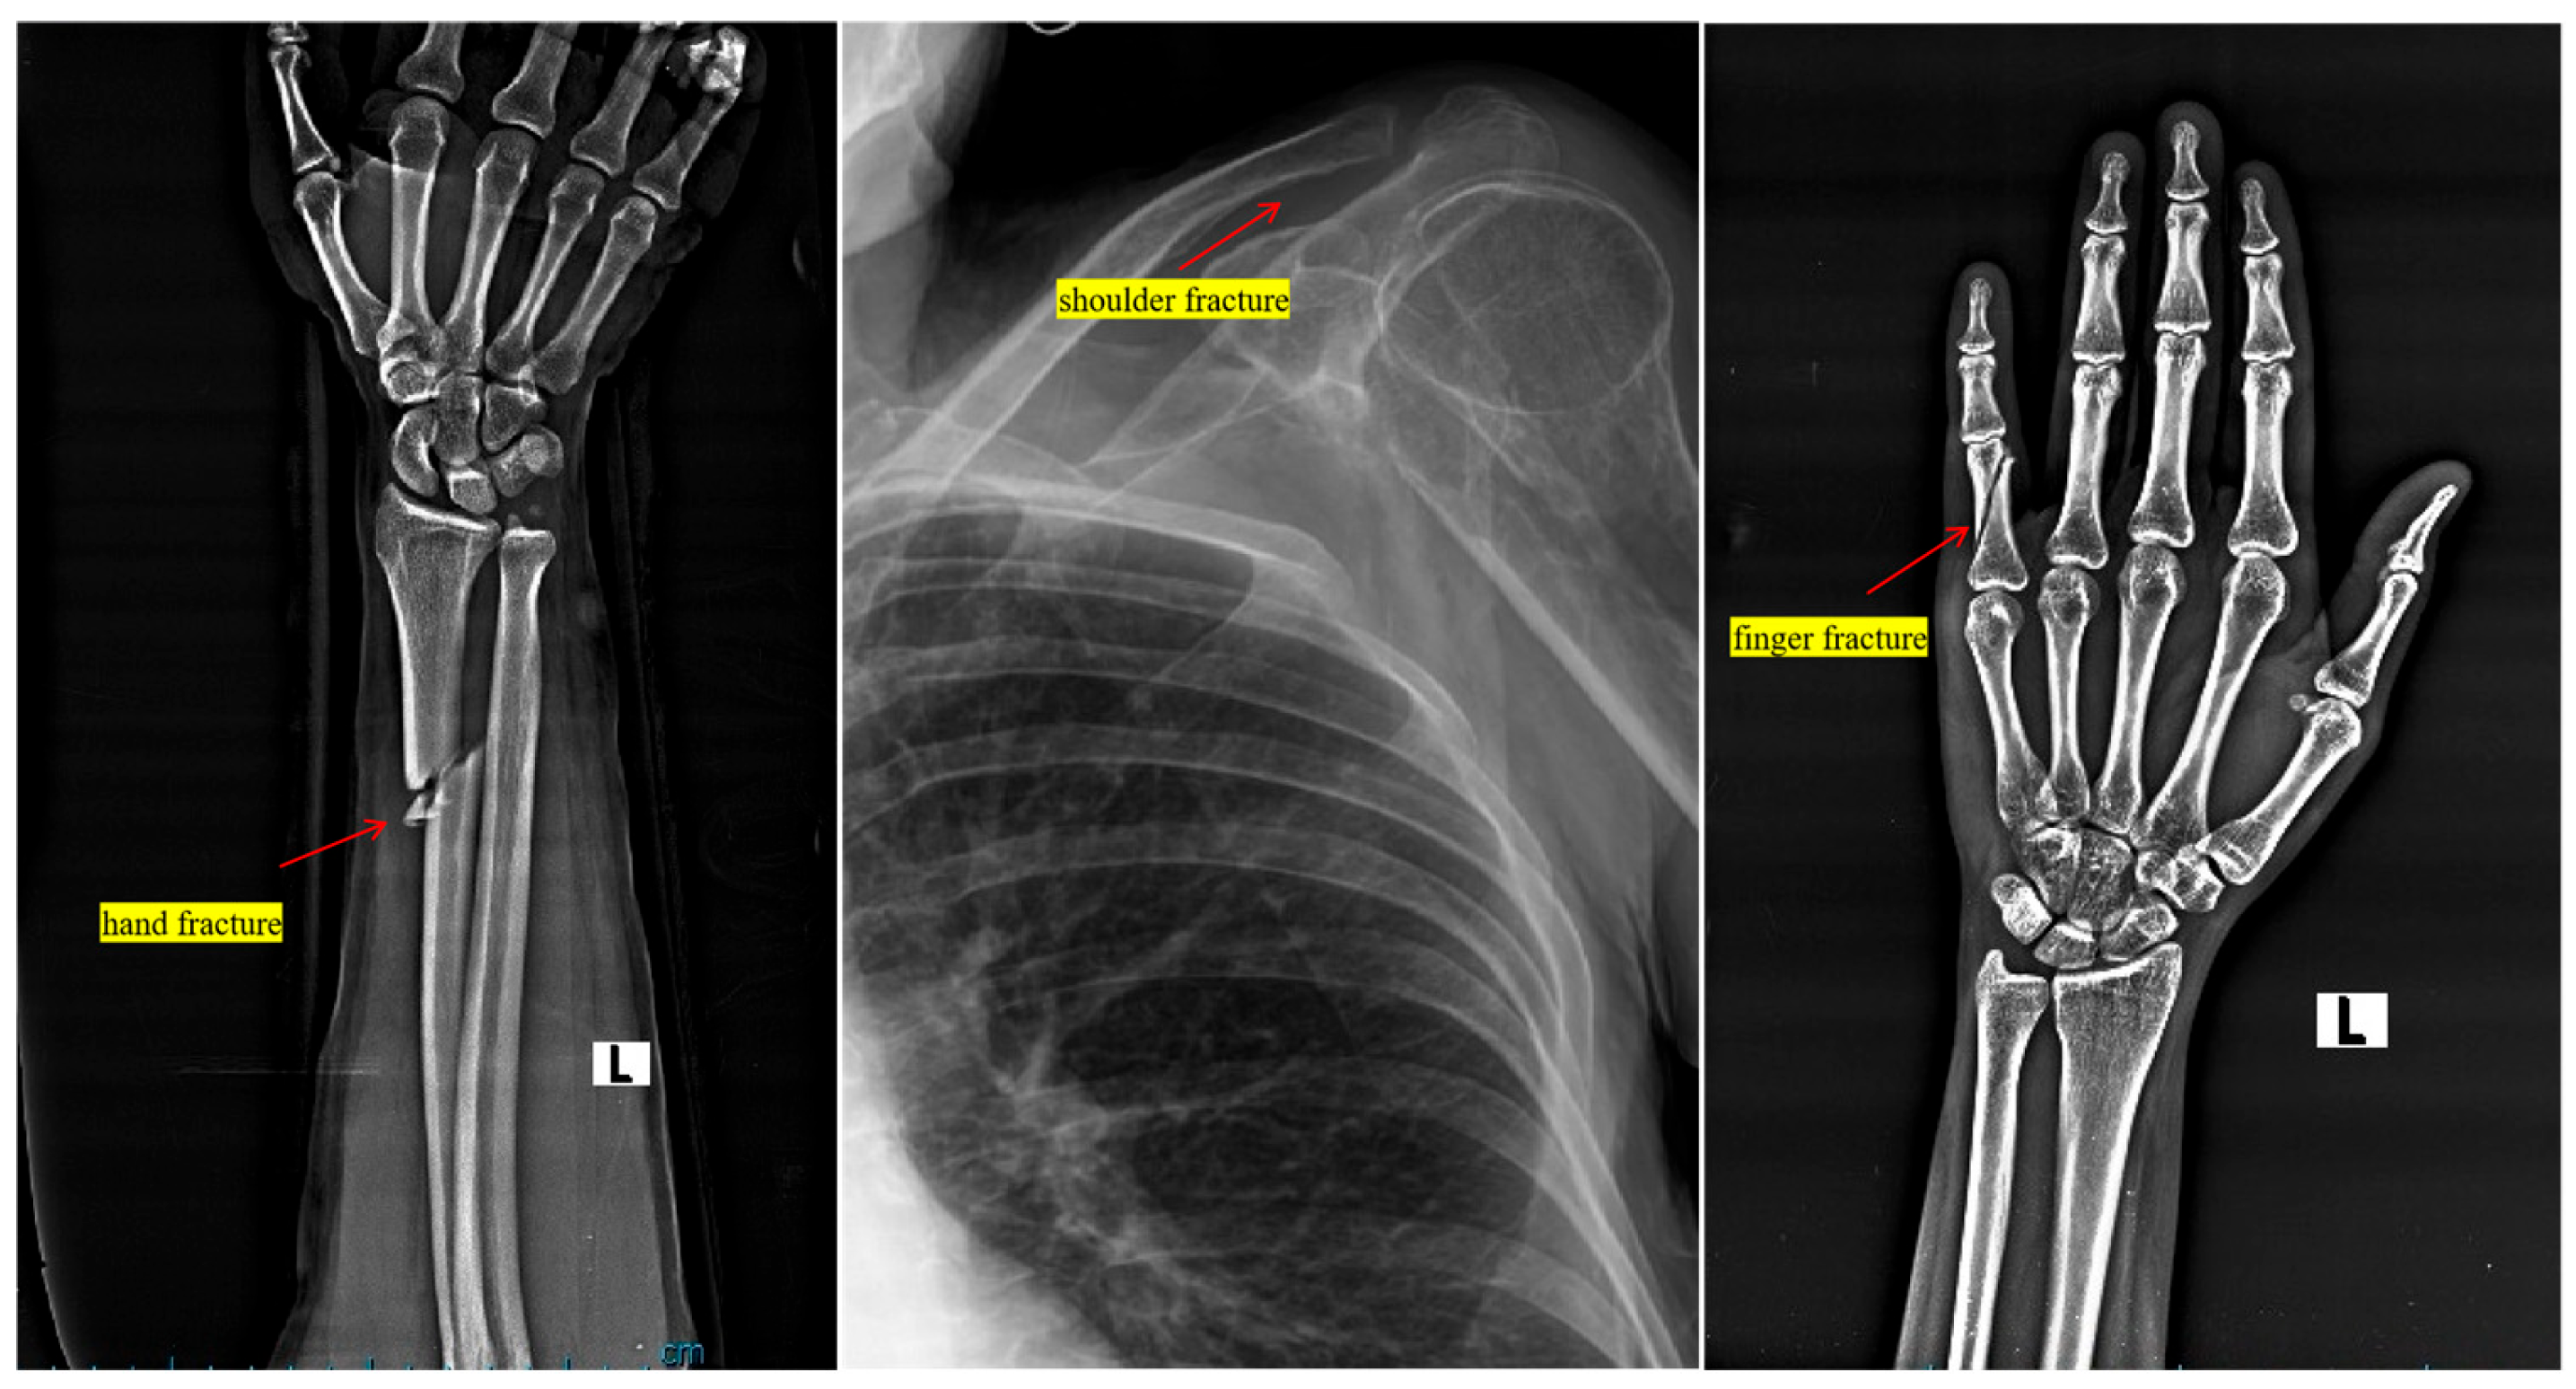

4.1. Dataset and Medical Image Preprocessing